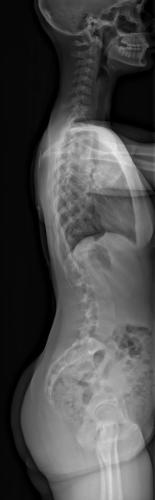

Images de scolioses opérées 16 janvier 202418 janvier 2023 par Damien Scoliose thoraco-lombaire 1 Radio préopératoire de Face Radio préopératoire de Profil Radio de Face à 2 ans de recul Radio de Profil à 2 ans de recul